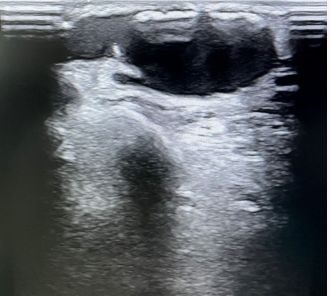

超声提示动脉瘤前瓣膜阻挡